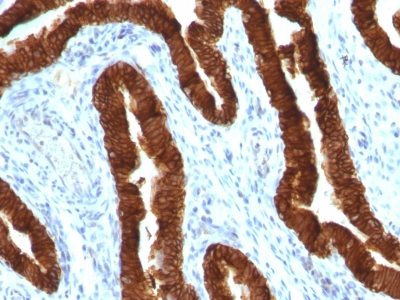

Recognizes a protein of 40 kDa, identified as cytokeratin-19 (CK19), which is expressed in sweat gland, mammary gland ductal and secretory cells, bile ducts, gastrointestinal tract, bladder urothelium, oral epithelia, esophagus, and ectocervical epithelium. Anti-CK19 reacts with a wide variety of epithelial malignancies including adenocarcinomas of the colon, stomach, pancreas, biliary tract, liver, and breast. Perhaps the most useful application is the identification of thyroid carcinoma of the papillary type, although 50%-60% of follicular carcinomas are also labeled. Anti-CK19 is a useful marker for detection of tumor cells in lymph nodes, peripheral blood, bone marrow and breast cancer.